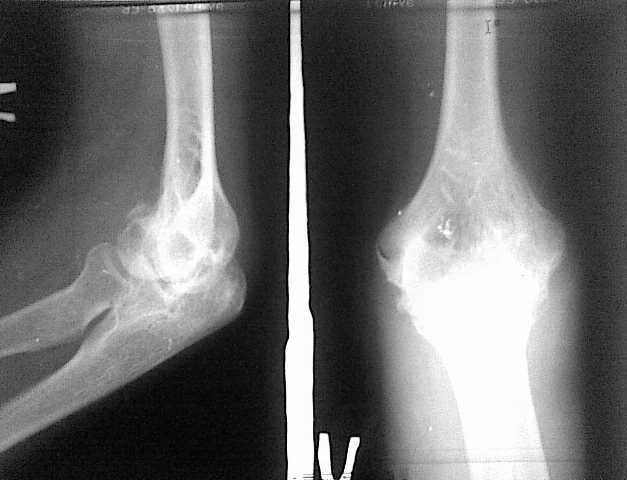

Контрактура локтевого сустава

4 месяца тому назад больная 20 лет прооперирована по поводу внутри суставного перелома наружного мыщелка плечевого сустава и локтевого отростка локтевой кости.

Отломки фиксированы спицами, наложен гипс на 45 дней. После снятия гипса отмечается стойкая смешанная контрактура локтевого сустава. Проведен курс физиотерапии, рассасывающие препараты. Амплитуда движений: сгибание 90, разгибание 110 градусов. Консервативное лечение без эффекта.